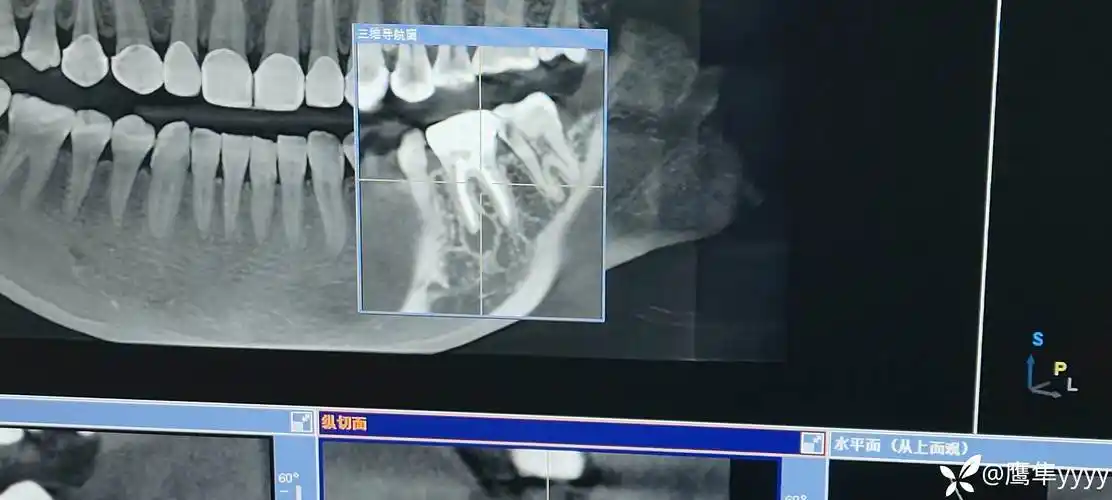

请问下大家我右下三号牙是根尖囊肿吗

求助本人患牙根管治疗后发现又出现一根尖囊肿求助各位大佬能不能保牙

记录一次根尖囊肿之前期保守根管治疗

病例根管治疗囊肿刮除根尖切除mta根尖封闭同期完成

各类根尖周病的x片表现